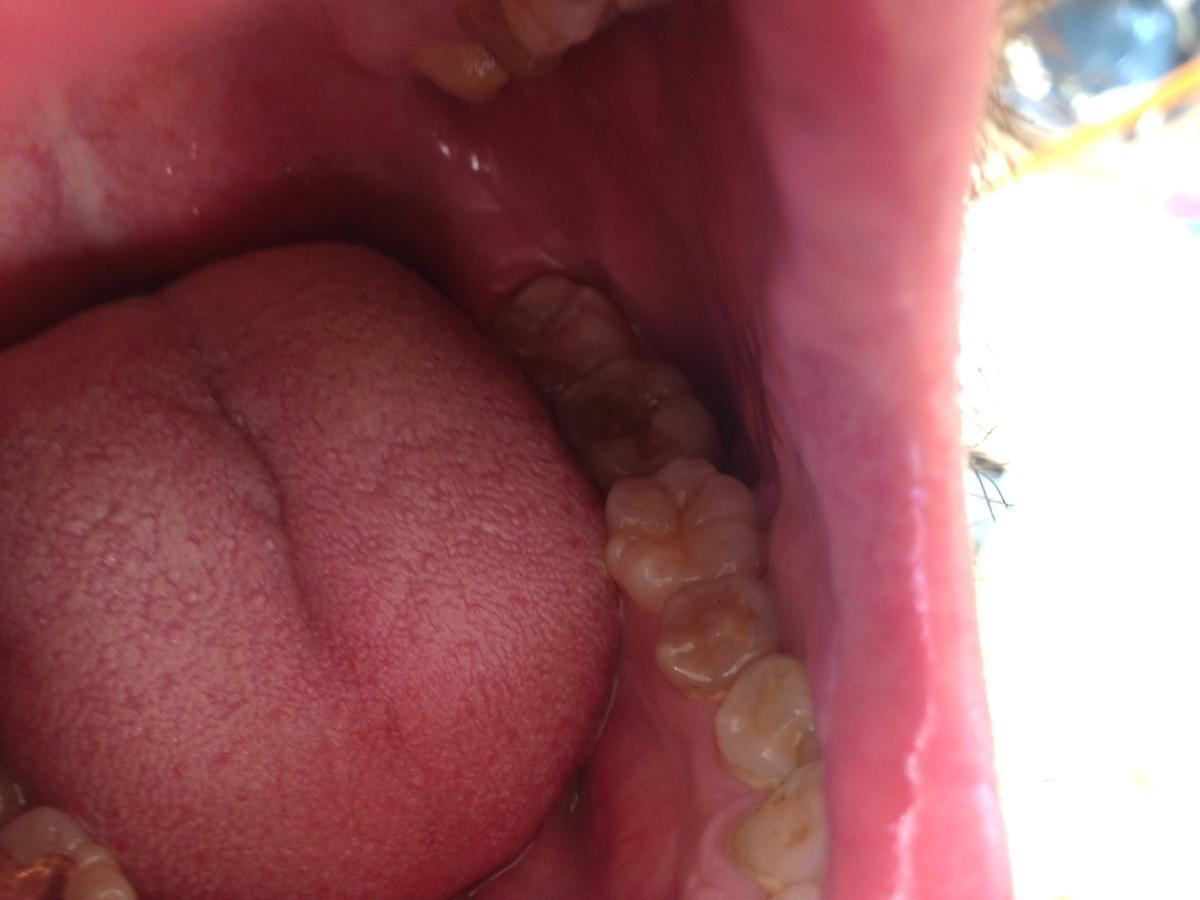

左下の銀歯を外し詰め物を詰めてた状態から詰め物を外した状態です。

左上は2本銀歯を外し詰め物を詰めてた状態から詰め物を外した状態です。

金歯を詰めました。

微調整して頂きました。完成です。